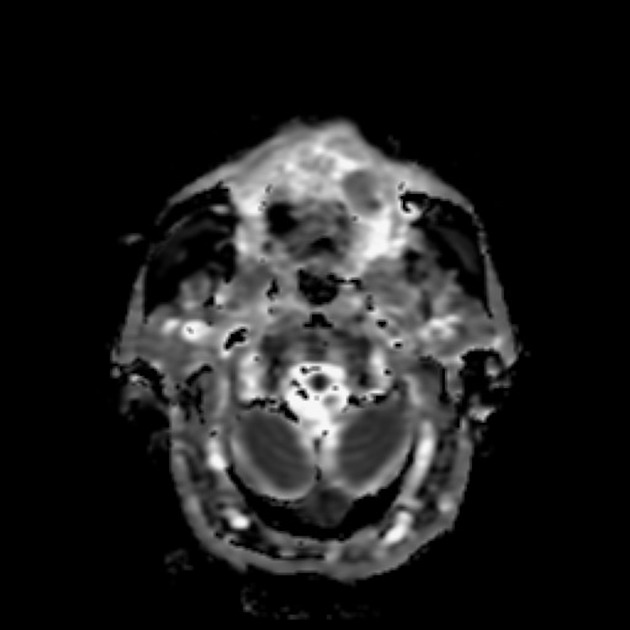

from mavink.com

Tongue Muscles Mri Anatomy

Tongue Muscles Mri Anatomy Tongue Piercing Mri The most common fear someone has when approaching the mri with piercings is having the piercings magnetically removed in a painful way, but a far lesser known and much more. Well, let’s take a look. Mri stands for magnetic resonance imaging, and it’s exactly what it sounds like. First of all, what is going on when you get an mri?. Tongue Piercing Mri.

Tongue Muscles Mri Anatomy Tongue Piercing Mri Well, let’s take a look. It can pull a stethoscope right out of a doctor's lab coat. So what would happen if you forgot to take out an earring? Mri stands for magnetic resonance imaging, and it’s exactly what it sounds like. It is common to see jewelry artifacts on imaging examinations, most commonly plain radiographs, although also on other. Tongue Piercing Mri.